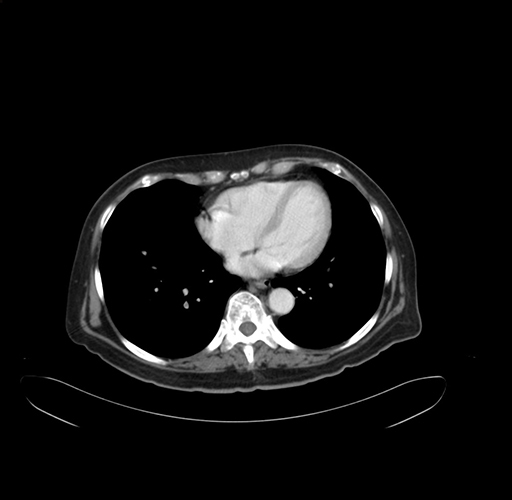

Pre-Chemo: Axial Venous

Axial Venous